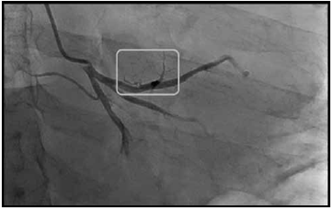

Al tercer día el paciente presenta de manera súbita pérdida del estado de conciencia en sala de quimioterapia, le documentan ausencia de pulso y activan protocolo de resucitación de la institución por lo que el servicio de emergencias acude a la sala de oncología. Se encuentra a un paciente con esfuerzo respiratorio agónico, monitorizado y con la presencia de taquicardia ventricular que progresa a asistolia, se procede a intubación en secuencia crash sin complicaciones, se realizan maniobras de resucitación por aproximadamente 20 minutos y se logra retorno a circulación espontánea, se documenta en ultrasonido a la cabecera del paciente derrame pericárdico sin evidencia de taponamiento, con pobre contractilidad, se descarta hemo o neumotórax, las cavidades cardiacas se encontraron de tamaños usuales, se realiza electrocardiograma (EKG) el cual documenta lesión subepicárdicas de la cara anterior, la cual no era conocida en EKG previo (Figura 1), se le da aviso a grupo de hemodinamia y se traslada a sala de procedimientos angiográficos donde realizan arteriografía coronaria de emergencia, que reporta coronarias epicárdicas sin evidencia de placas arterioescleroticas; sin embargo, en la arteria descendente anterior reportan que "se observan ramas anteriores hacia una estructura que no se logra identificar en el aspecto más anterior, superior y proximal de la arteria y que podría corresponder a pequeñas fístulas a un hemangioma o irrigación de estructura neoplásica infiltrante" (Figura 2), se hace ecocardiograma posparo que documenta deterioro de la eyección a 35% con aquinesia anterior tercio distal y con imagen compatible con trombo apical, con derrame pericárdico moderado sin evidencia de taponamiento cardiaco. Así mismo se obtuvo una radiografía de tórax pos paro donde es evidente la masa mediastinal (Figura 3).